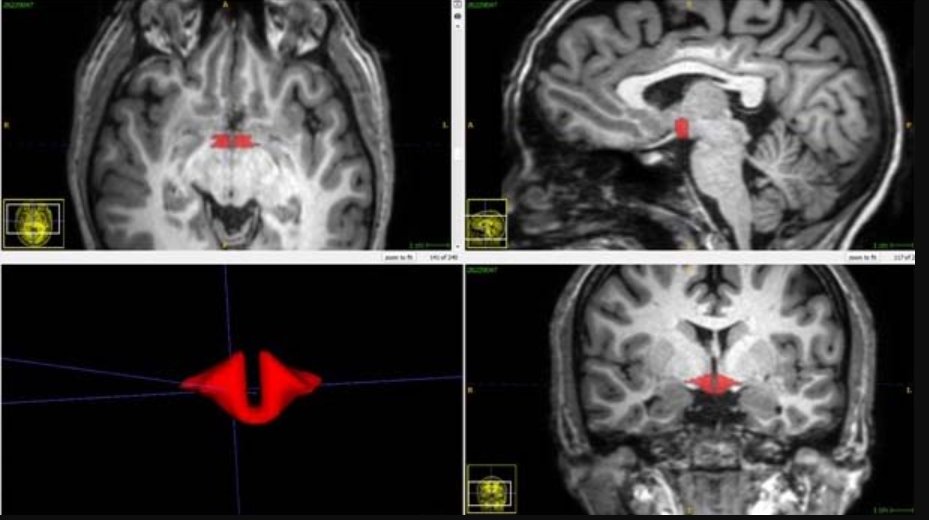

شاركت في التجربة 50 امرأة سليمة بلا أمراض، استخدمت 21 سيدة منهنّ حبوب منع حمل تحتوي على هرمونات الاستروجين Estrogen والبروجيستين Progestin الاصطناعية بانتظام. وتمّ تصوير أدمغتهم بأشعة الرنين المغناطيسي لدراسة أي تغييرات بين المجموعتين.

بدَت النتائج واضحة بعد التصوير؛ منطقة ما تحت المهاد أصغر بحوالي 6% في السيدات اللاتي تناولنَّ تلك الهرمونات. قد تبدو النسبة صغيرة جدًا، لكنها ليست كذلك في هذه المنطقة بالذات. لاسيما إن علِمنا أنها ضئيلة كحبة فاصولياء. نتيجة مهمة وبحاجة إلى تمحيص أكبر لمعرفة الأسباب.